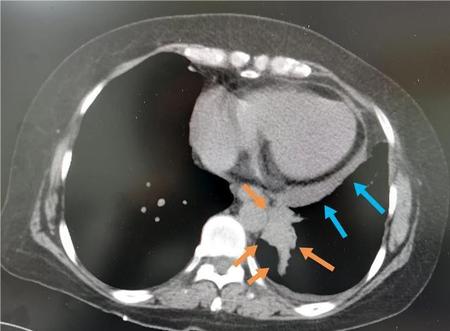

这位老年女性咳嗽一个月,CT发现左侧肺癌晚期,已经侵犯胸膜并引起心包积液,没有根治机会了。